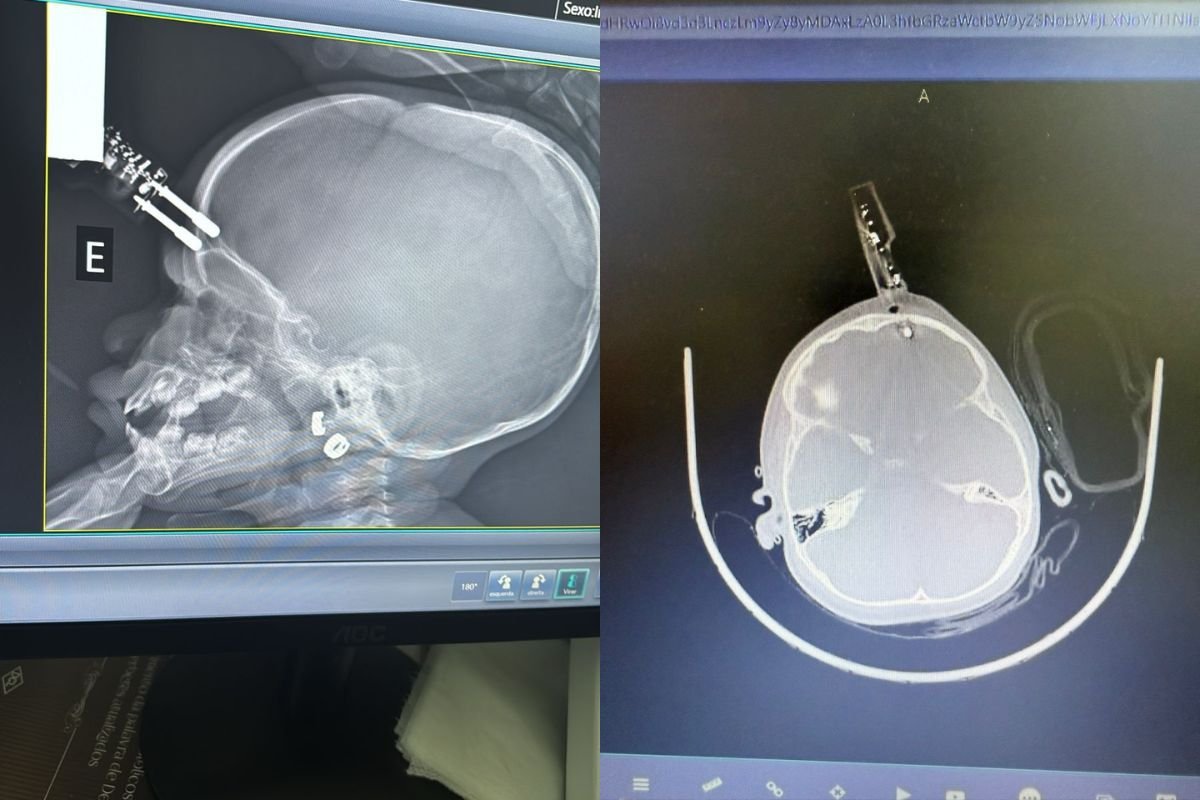

Uma menina de 1 ano passou por uma cirurgia de urgência após sofrer um acidente doméstico em Divinópolis, na última terça-feira (13). A criança caiu da cama e teve um carregador de celular cravado na testa, próximo à região do olho. Segundo o neurocirurgião Bruno Castro, responsável pelo atendimento, a menina segue internada em observação, sem sinais de sequelas neurológicas até o momento.

A menina foi levada imediatamente ao bloco cirúrgico, onde passou por procedimentos de retirada do objeto, limpeza, lavagem, fechamento e reconstrução da área atingida.

Segundo o especialista, o principal risco foi a lesão cerebral, já que o objeto perfurou o osso do crânio e atingiu o tecido cerebral. “Isso pode ocasionar hemorragia”, explicou.